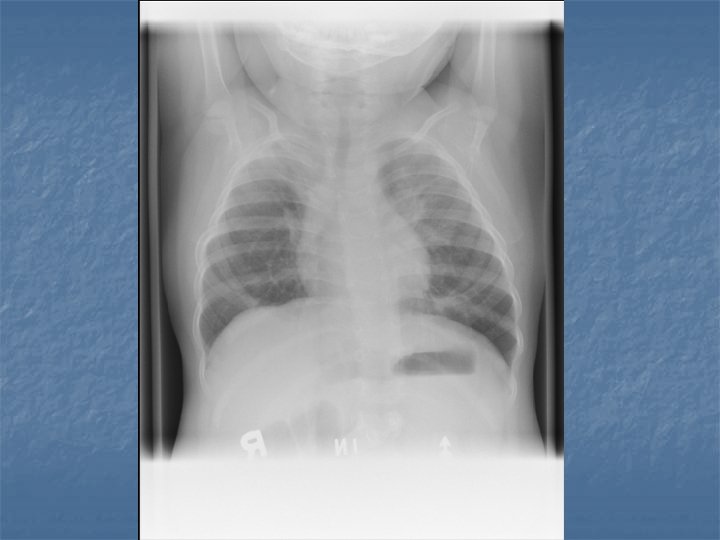

Case AJ: 11 yo male n n n N/V/D x 1 day 6 x vomitting, 2 x diarrhea Periumbilical abdo pain “Dizzy” Rhinitis, cough 38 C, HR 117, RR 28, 105/75, 96% RA

AJ’s Exam n n n Pale Small cervical nodes Abdo exam nontender No indrawing Decreased breath sounds RLL, crackles

Pediatric CAP n n Bronchopneumonia – acute inflammation smaller bronchial tubes and peribronchiolar alveoli Pneumonitis Syndrome – Infants 1 – 3 months old, afebrile with cough, tachypnea and progressive respiratory distress. n n CXR shows diffuse pulmonary infiltrates and air trapping Single or mutlipathogens involved

CXR Findings VIRAL n Peribronchial thickening n Diffuse interstitial infiltrates n Hyperinflation BACTERIAL n Subsegmental, segmental or lobar infiltrates n Air bronchograms n Round pneumonia in early S. pneumo n n M. pneumo diffuse infiltrates out of proportion to clinical findings (or bronchopneumonia infiltrates in lower lobes) Bilateral reticulonodular interstitial infitrates

n n n 50% bacterial pneumonia will have lobar infiltrate Can also see alveolar infiltrates Round pneumonia seen with S. pneumo